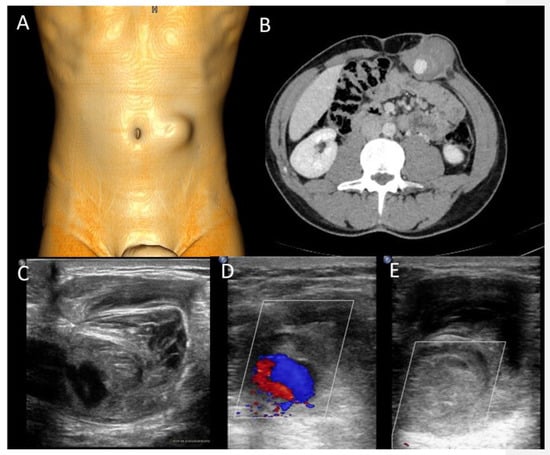

Figure 9. A 37-year-old man presenting with a pulsatile mass with trauma history. Volume rendering cutaneous reconstruction (A) and axial, contrast-enhanced portal-phase CT (B) showed the presence of a large post-traumatic pseudoaneurysm of the inferior right epigastric artery, with thrombotic apposition. B-mode US and CDUS (CE) demonstrate the presence of an anechoic part, corresponding to the contrast-enhanced part on CT, and the heterogeneity of the thrombus. CDUS (D,E) shows the “yin–yang sign”. The pseudoaneurysm was promptly treated with thrombin injection.